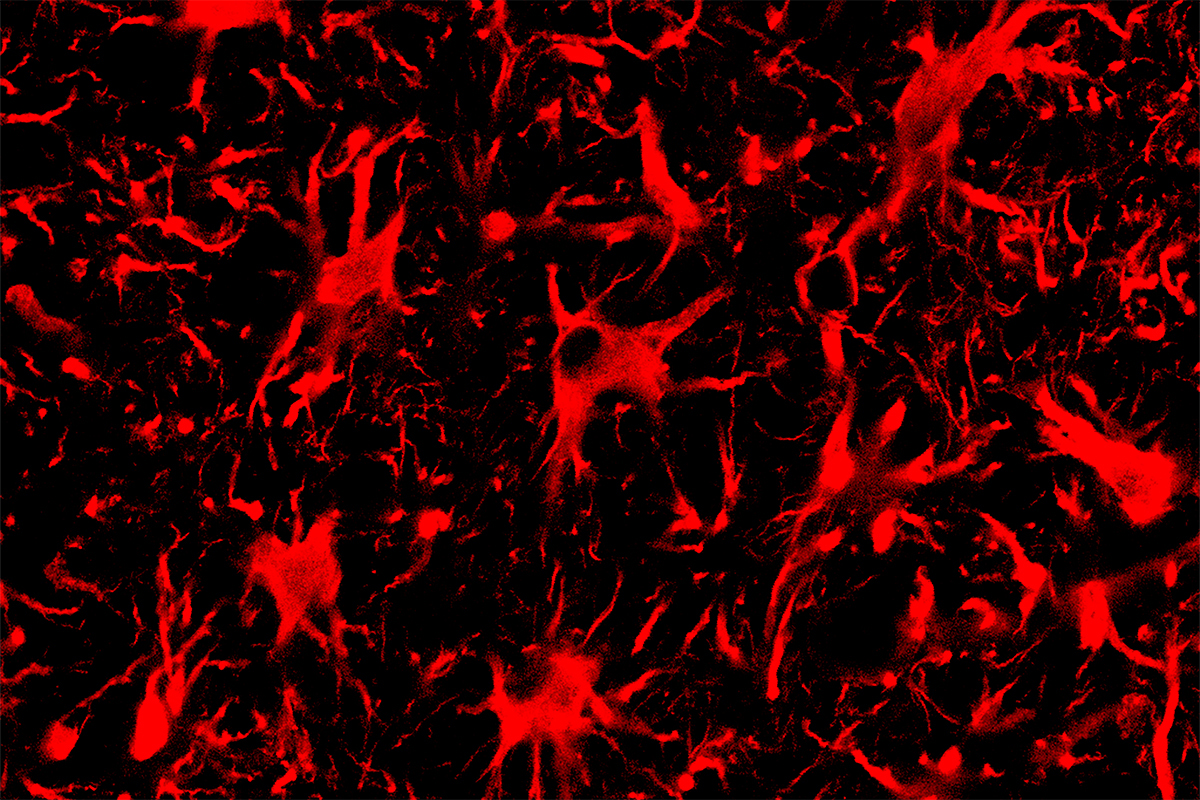

A single genetic mutation can have profound consequences, as demonstrated in neurodegenerative diseases such as amyotrophic lateral sclerosis or Huntington’s disease. A new study by University of Illinois Urbana-Champaign researchers used a targeted CRISPR technique in the central nervous systems of mice to turn off production of mutant proteins that can cause ALS and Huntington’s disease.

The researchers injected the CRISPR-Cas13 systems to the central nervous systems of mice with genetic mutations that cause ALS or Huntington’s disease. Adeno-associated virus vectors carried the RNA-targeting systems to cells. These vectors are a promising vehicle for gene therapy due in part to their ability to enter cells within the spinal cord and brain, Gaj said.

The researchers found that CRISPR-Cas13 effectively reduced the amount of mutant protein present in the nervous system for both diseases – specifically, the protein SOD1 within the spinal cords of mice with ALS, and the protein “huntingtin” within the brains of mice with Huntington’s disease. The reduction in mutant SOD1 protein also correlated with better therapeutic outcomes: Mice with ALS that received the CRISPR-Cas13 injection had slower disease progression, improved survival and a slower rate of decline in grip strength and motor skills compared with mice that did not receive the treatment.